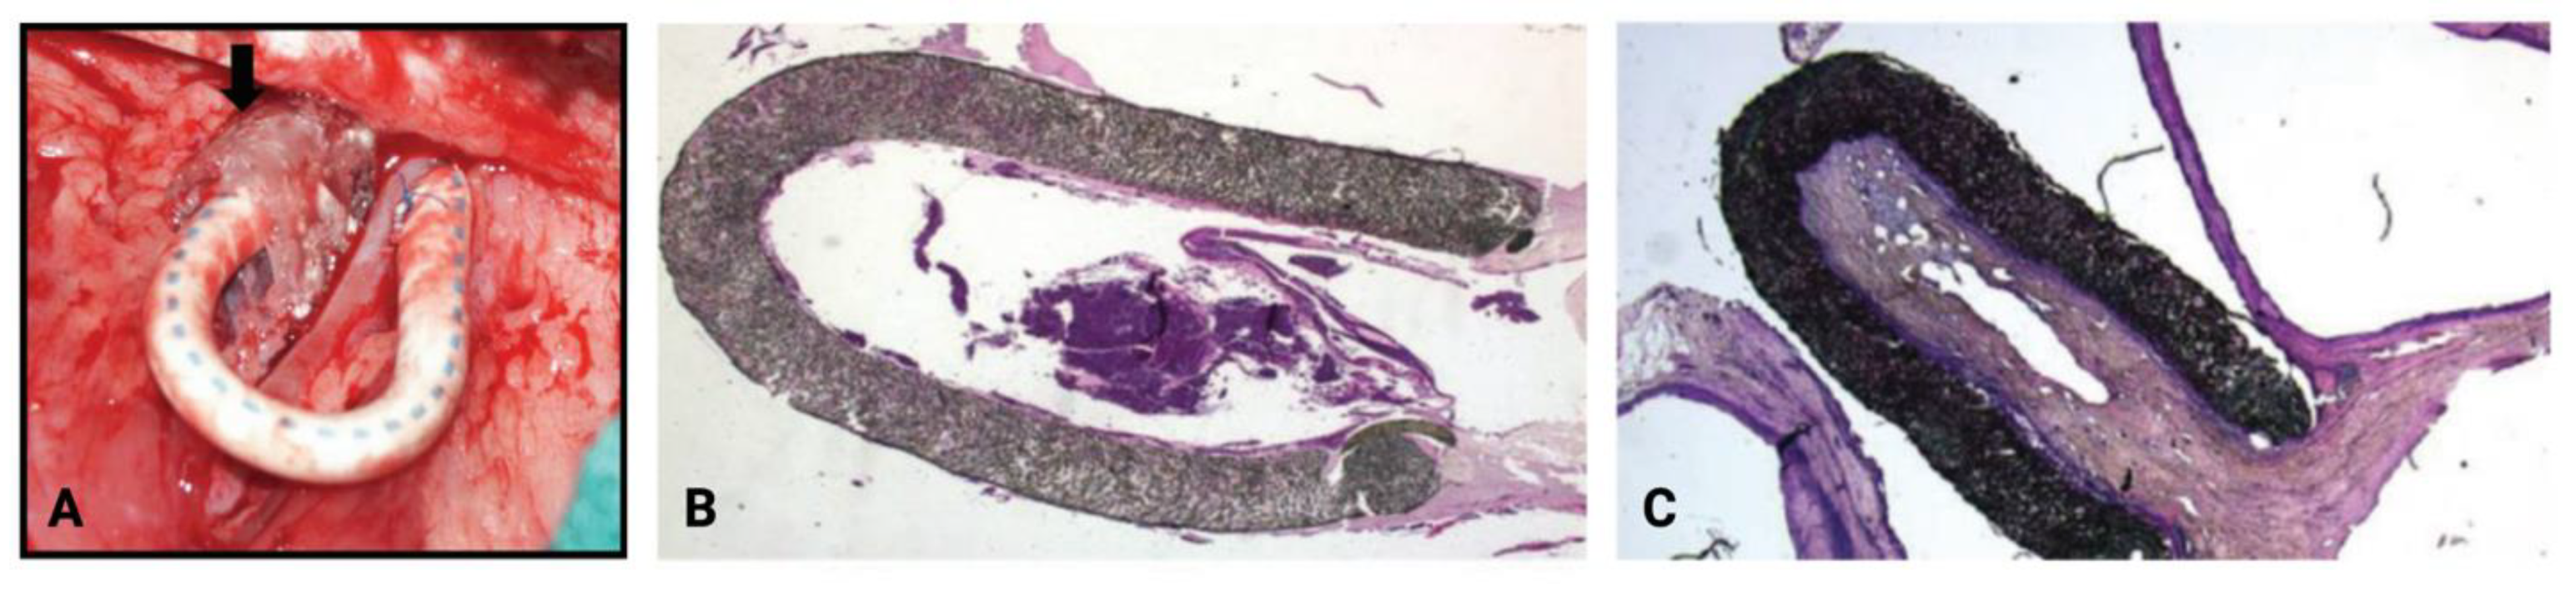

- Brahmbhatt, A.; NievesTorres, E.; Yang, B.; Edwards, W.D.; Chaudhury, P.R.; Lee, M.K.; Kong, H.; Mukhopadhyay, D.; Kumar, R.; Misra, S. The Role of Iex-1 in the Pathogenesis of Venous Neointimal Hyperplasia Associated with Hemodialysis Arteriovenous Fistula. PLoS ONE 2014, 9, e102542. [Google Scholar] [CrossRef]

- Singh, A.K.; Cai, C.; Kilari, S.; Zhao, C.; Simeon, M.L.; Takahashi, E.; Edelman, E.R.; Kong, H.; Macedo, T.; Singh, R.J.; et al. 1α,25-Dihydroxyvitamin D3 Encapsulated in Nanoparticles Prevents Venous Neointimal Hyperplasia and Stenosis in Porcine Arteriovenous Fistulas. J. Am. Soc. Nephrol. 2021, 32, 866. [Google Scholar] [CrossRef]